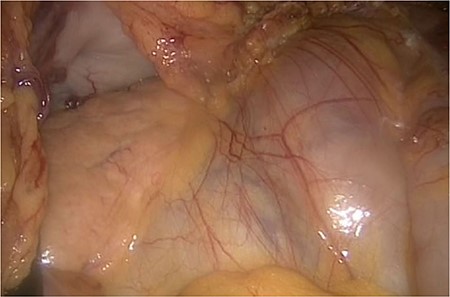

The slim intraperitoneal appendix in the left upper corner with the covered terminal ileum. In the right lower corner, the covered ileum convulse is seen.

Even the terminal ileum seemed to be retroperitoneal. The slim preperitoneal appendix and the terminal retroperitoneal ileum are demonstrated in Fig. 4. The entire ileum was covered by the peritoneum.